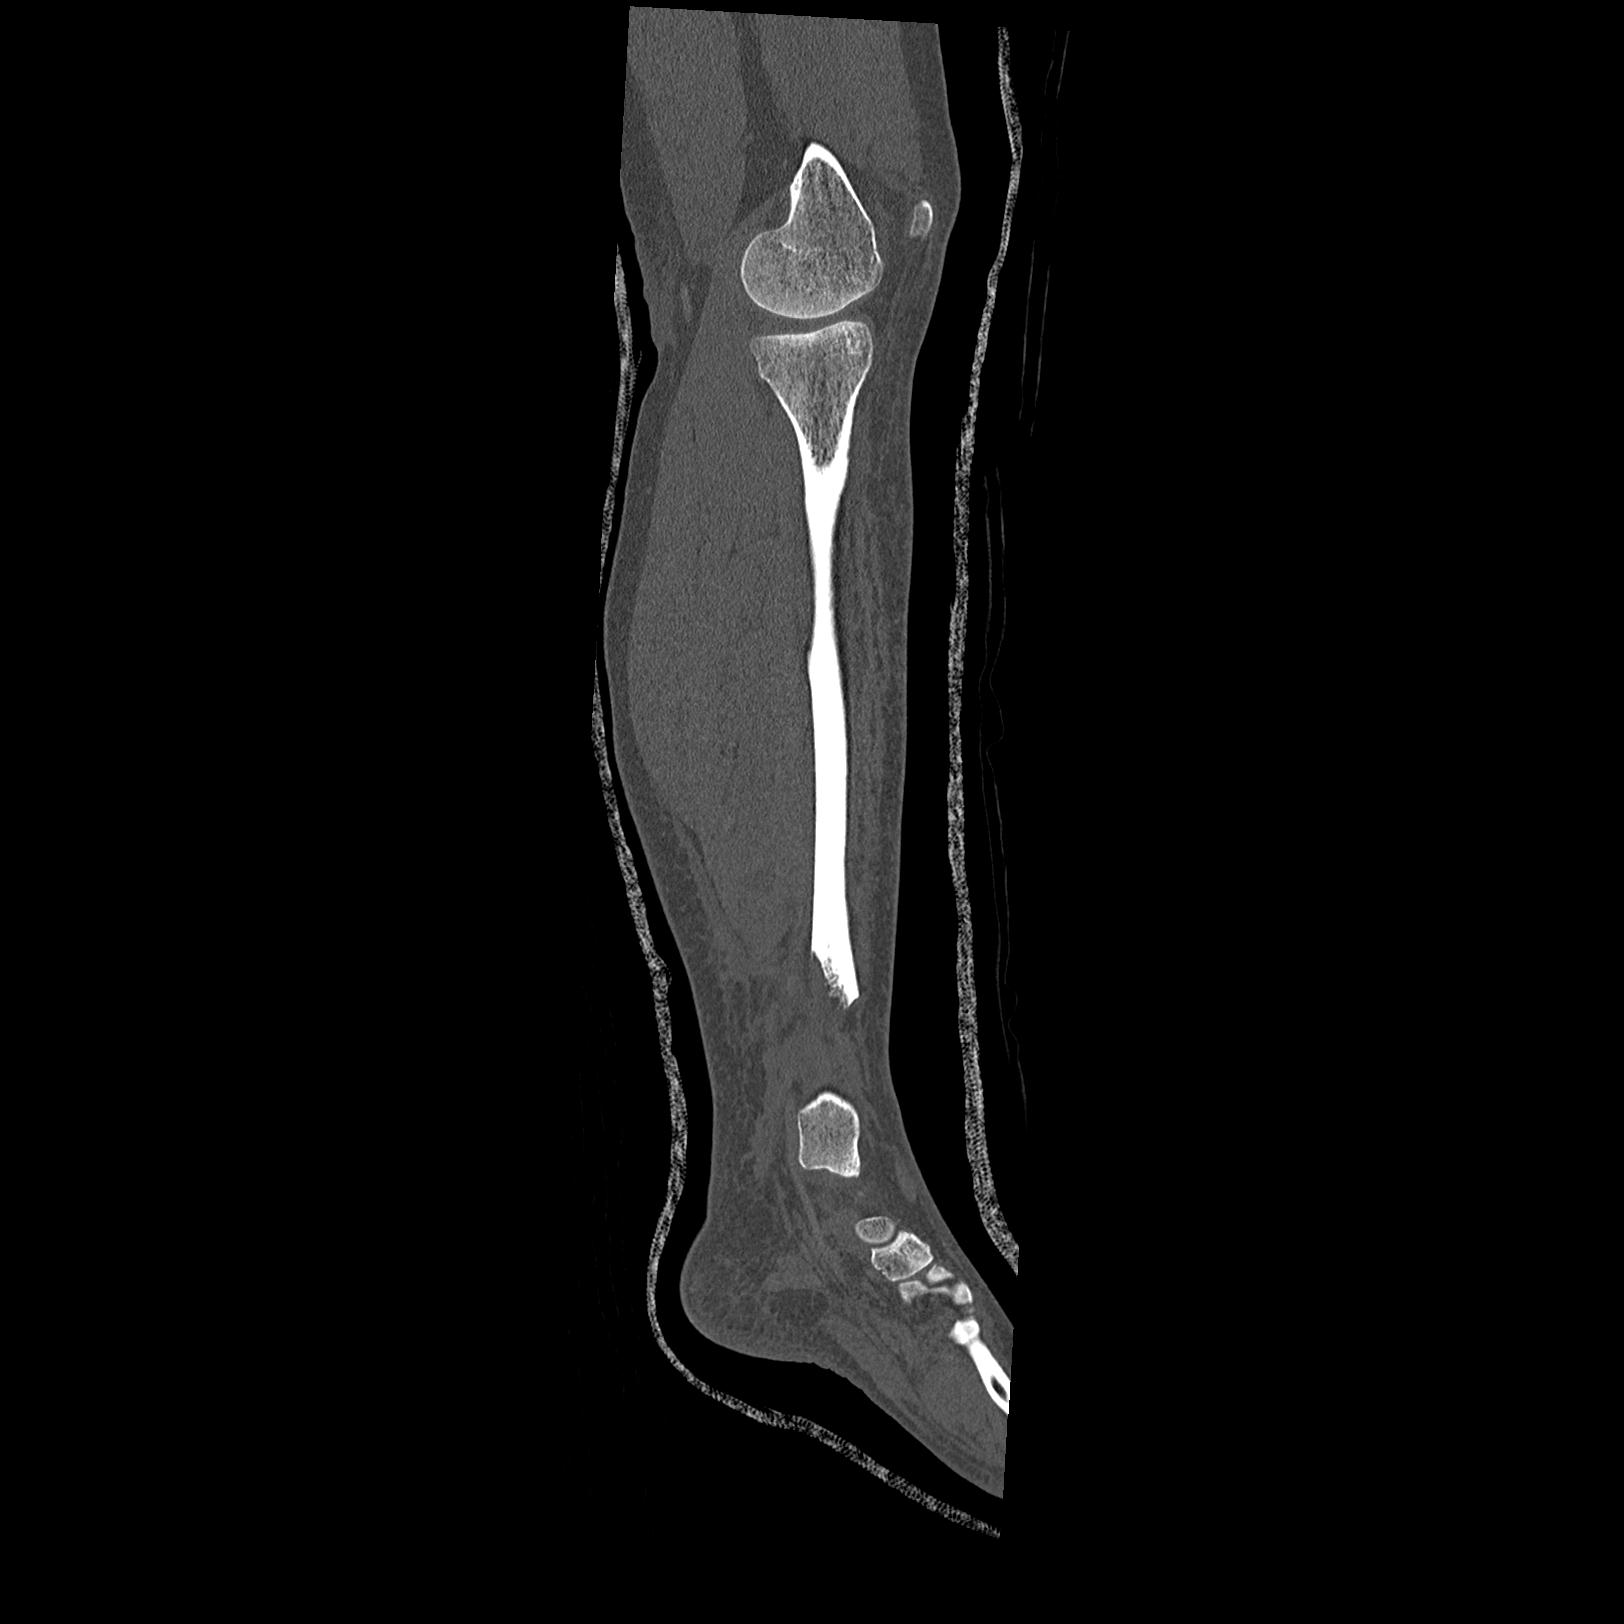

102803 1/12(キウスなし) 1/27 左下腿 4R 30歳女性 左脛骨軸内釘